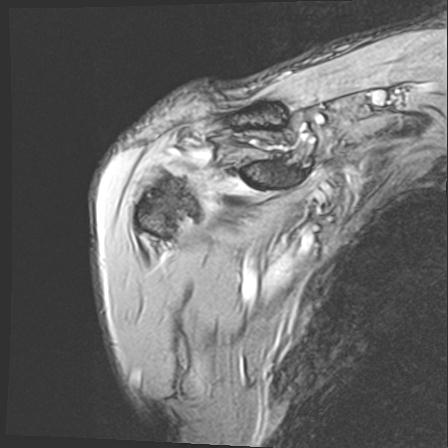

60058 3/9 11/4 右肩 2R+MRI 73歳男性 肩腱板損傷